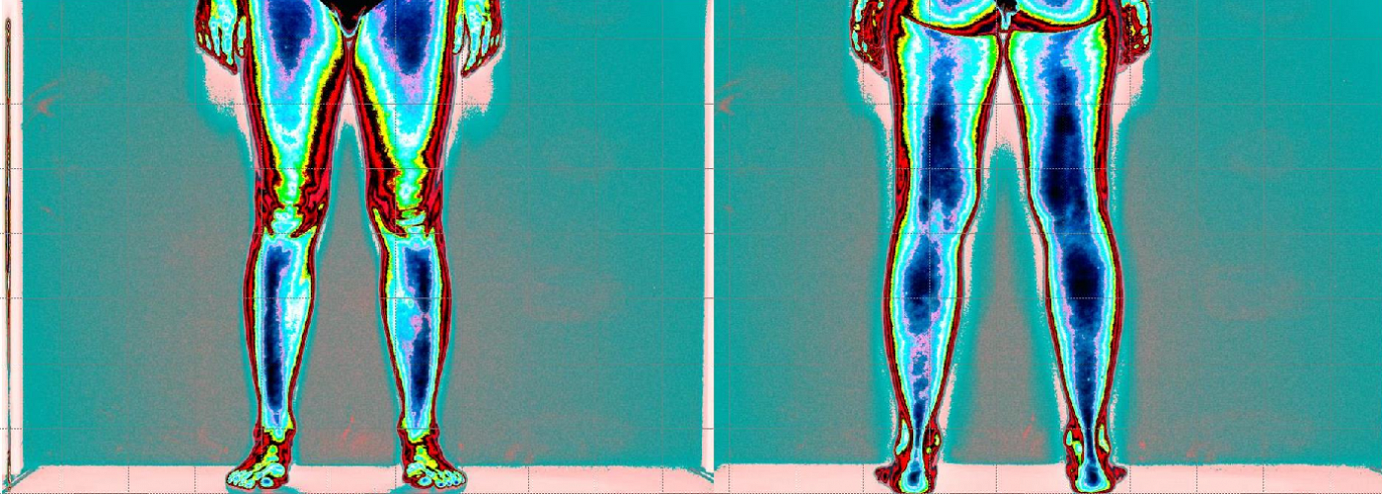

Nella foto si evince assenza di attivazione muscolare degli arti inferiore (colore rosso)

Ipertono della tensione muscolare (colore blu scuro) a compenso della catena anteriore.

(colore verde azzurro e uniformità nella tensione muscolare)